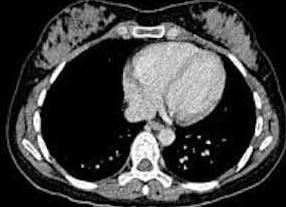

КТ применяется для диагностики заболеваний многих органов и систем уже на протяжении тридцати лет. Исследование проводится с помощью специального аппарата – компьютерного томографа. В основе метода лежит рентгеновский луч, который пронизывая исследуемый орган по спирали, выполняет последовательные сканы с частотой в несколько миллиметров. Результат фиксируется на рентгеновской пленке, в виде поперечных срезов (томограмм).

Компьютерная томография (КТ) молочных желез – метод компьютерной рентген-диагностики, позволяющий получать послойное сканирование тканей молочных желез. Во время выполнения компьютерной томографии пациентка лежит на горизонтальной плоскости в цилиндрической камере с рентгеновским излучателем и датчиком. Изображение каждого среза передается в компьютер, где обрабатывается и суммируется с другими данными. КТ молочных желез дополняет обзорную маммографию и используется для уточнения распространенности и операбельности опухолевого процесса, заинтересованности лимфоузлов, прорастания опухоли в грудную стенку.

Больная размещается на специальном выдвижном столе, после чего перемещается внутрь томографа. Важно занять удобное положение, чтобы исключить любые движения во время проведения исследования, так как это может стать причиной искажения изображений. Персонал уходит в соседний кабинет. После этого специалист включает прибор и приступает непосредственно к обследованию. Наблюдение за состоянием пациентки и ходом манипуляции осуществляется через окно, соединяющее оба помещения. Также в томографе присутствует устройство для двухсторонней связи. Некоторые модели оснащены кнопкой экстренного вызова. Во время КТ молочных желез рентгеновские лучи падают на исследуемую зону под разными углами, полученные данные обрабатываются компьютером и отображаются на экране монитора, таким образом, формируются многочисленные сканы.